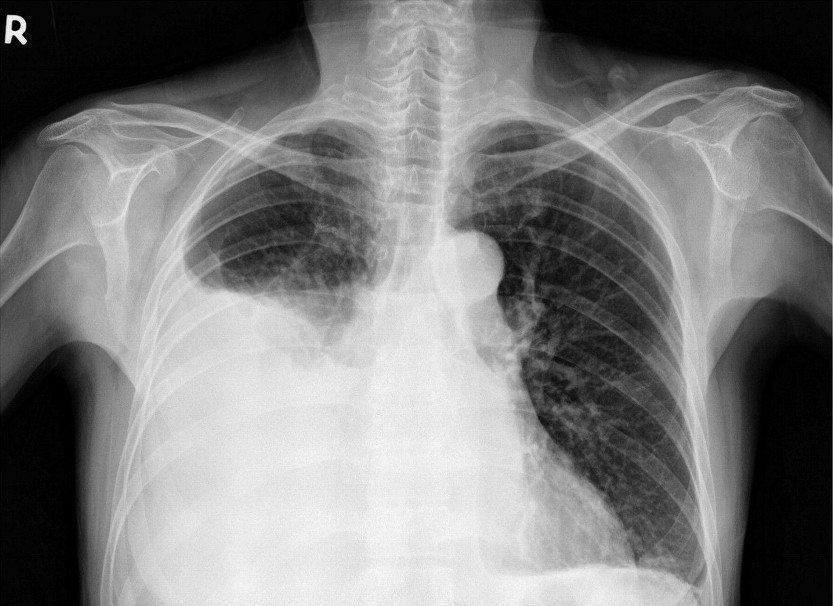

Диагностика

Для точного выявления причины накопления жидкости и назначения соответствующего лечения врачу необходимо провести диагностику. Обследование пациента осуществляется в несколько этапов. Сначала анализируют оба легких, используя следующие методы:

- визуализацию грудной клетки — при некоторых заболеваниях может изменяться форма грудной клетки;

- определение болевых зон;

- ультразвуковое исследование;

- лабораторное исследование жидкости.

Кроме того, назначается анализ крови, в котором оценивают уровень газов в биоматериале, наличие опухолевых маркеров и показатели свертываемости.

Поскольку существует множество возможных причин данного состояния, третий этап диагностики сосредоточен на их выявлении. Врачи уделяют особое внимание функционированию печени, почек и сердца. Пациенту могут быть назначены:

- Общий анализ мочи.

- Ультразвуковое исследование.

- Компьютерная томография.

- Магнитно-резонансная томография.